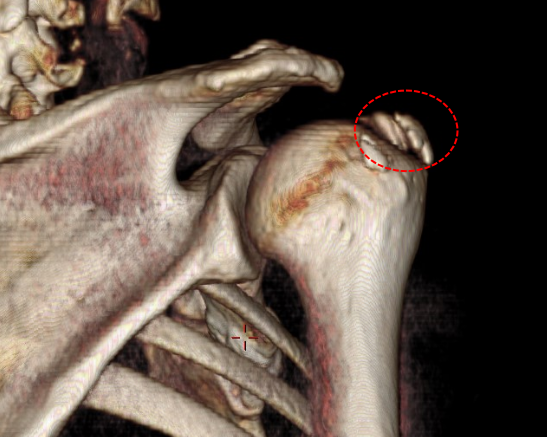

这种疾病名为肩关节钙化性肌腱炎,肩关节钙化性肌腱炎是肩部肌腱内钙盐异常沉积引发的炎症性疾病,常见于40-50岁人群,以肩部剧烈疼痛、活动受限为主要表现。钙化性肌腱炎是肌腱组织内出现羟基磷灰石晶体沉积的病理状态,肩袖肌腱(尤其是冈上肌腱)最常受累。钙盐沉积可能与肌腱局部缺氧、代谢异常或退行性变有关,导致炎症反应和机械性刺激,引发疼痛和活动障碍。急性期疼痛剧烈,夜间加重,可能放射至上臂;抬手、外展或旋转动作困难,严重时影响穿衣、梳头等日常活动。肩峰下或肱骨大结节处压痛,部分患者伴局部肿胀。若钙化灶>1.5cm,往往需关节镜手术治疗。

门诊医生立即为黄阿姨办理了住院,并于当天晚上完成急诊手术,通过3个0.5cm小切口在关节镜下解决了病因。镜下可见冈上肌腱内冒出牙膏状钙化沉积物,彻底清理后缝合肩袖破口。